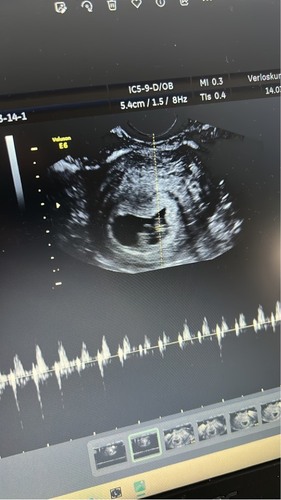

Gekke echo

Goedenavond, Wat zouden jullie zeggen als jullie deze echo bekijken. De verloskundige dacht niet aan een 2e vruchtje maar wist ook niet wat het dan wel was. Ik heb pas volgende week donderdag weer een echo. Voel me erg onzeker 馃槥

Jajanee

Vast niks ergs. Zal voor je duimen